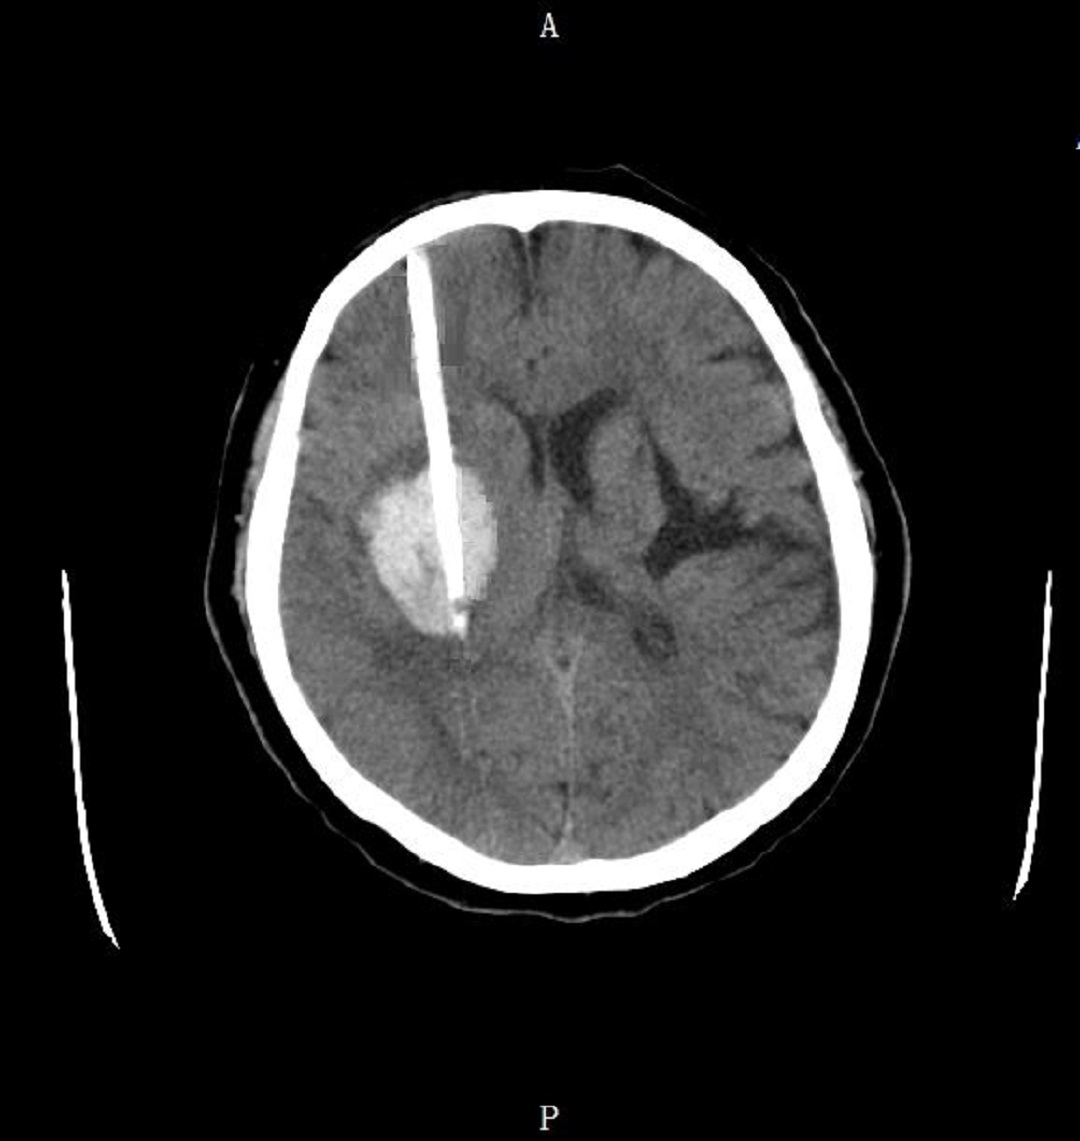

術(shù)前將導(dǎo)板放于術(shù)區(qū),標(biāo)記穿刺體表位置。術(shù)區(qū)消毒,橫切口長3cm,鉆骨孔切開硬腦膜,以鼻根及額部標(biāo)記,將導(dǎo)板用無菌薄膜包好后置于病人面部,使模型與病人面部緊密吻合,12號顱腦引流穿刺器放入穿刺通道內(nèi),緊貼內(nèi)壁,緩慢推進(jìn)至設(shè)定深度(9.5cm)拔出針芯,可見陳舊性血性液流出,固定引流管,一次性成功穿刺血腫,手術(shù)操作時間僅用15 min。(見下圖):

術(shù)后當(dāng)天CT